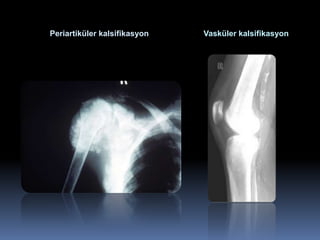

periostal resorpsiyon ve arterial kalsifikasyon

Paratiroidektomi öncesi   Paratiroidektomi sonrası

Periartiküler kalsifikasyon   Vasküler kalsifikasyon

Sekonder hiperparatiroidide periostal resorpsiyonve arterial kalsifikasyon Paratiroidektomi öncesi Paratiroidektomi sonrası